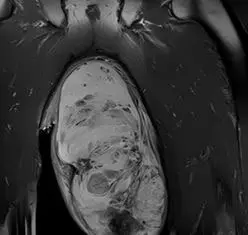

CT(컴퓨터단층촬영)과 MRI(자기공명영상) 검사 결과, 왼쪽 음낭 안에서 가로 25cm, 세로 15cm 크기의 거대한 덩어리가 발견됐다. 의료진은 곧바로 왼쪽 음낭을 25cm가량 절개해 덩어리를 제거하는 수술을 시행했다. 다행히 음낭 안에 있는 고환과 부고환에는 이상이 없는 것으로 확인됐다. 조직검사 결과, 이 덩어리는 혈관근섬유모세포종으로 진단됐다.

혈관근섬유모세포종은 대부분 통증 없는 작은 덩어리로 시작한다. 시간이 지나 크기가 커지면 음낭이 부어오르거나 불편감을 유발할 수 있으며, 종양 내부에 혈관이 많아 출혈이나 부종이 생기기도 한다. 혈관근섬유모세포종은 먼저 초음파 검사로 종양의 위치와 경계를 파악한다. 이후 주변 조직 침범 여부 확인하기 위해 MRI와 CT 검사를 진행한다. 마지막으로 수술적 절제 후 조직검사를 통해 확정 진단을 내린다.